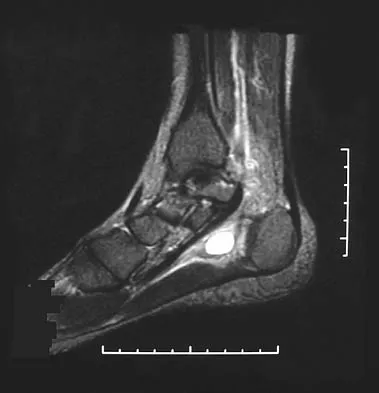

A 28-year-old professional dancer reports a 3-month history of progressive pain in the posterior aspect of the left ankle. Her symptoms are worse when she assumes the en pointe position. Examination reveals tenderness to palpation at the posterolateral aspect of the ankle posterior to the peroneal tendons which is made worse with passive plantar flexion. There is no nodularity, fluctuance, or tenderness of the Achilles tendon. The neurovascular examination is unremarkable. A lateral radiograph and MRI scan are shown in Figures 16a and 16b, respectively. Management should consist of